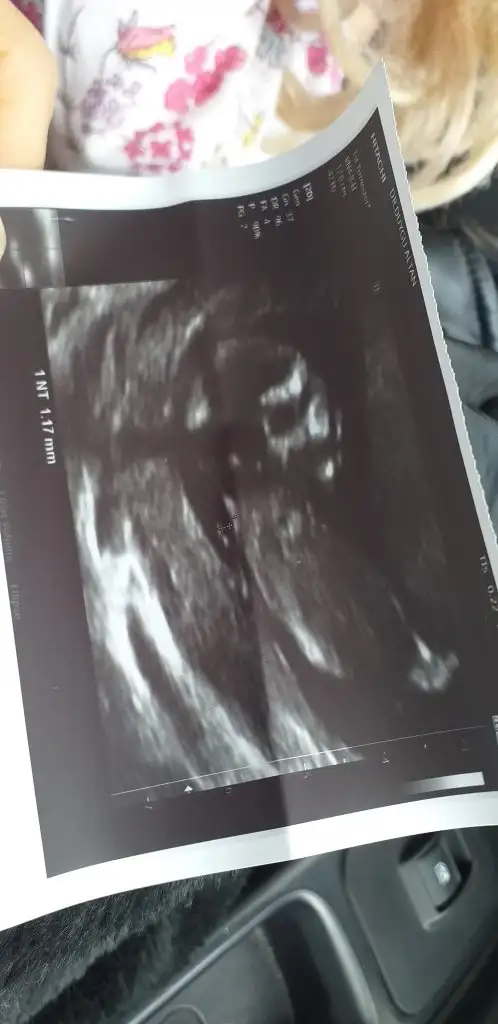

Yok ikinci ilki kız bugün doktor erkek görüyorum dedi hayırlısı olsun 13+2Erkektir o zamankaç haftalık şimdi ilk bebekmi

Dr la tahminim aynıYok ikinci ilki kız bugün doktor erkek görüyorum dedi hayırlısı olsun 13+2

Kaç haftalık usg sanki erkek gibi 11 12 13 haftalar olmalıIkra meyra 13 haftalık yorum yaparmısınız

11 12 13 hafta olmalı kız sanki emin olamadımTahmin yaparmisiniz kızlar

Erkek gibi geldi bana yandan pozisyon daha iyi olurdu 13 haftayıda paylaşınBu da 11+2 arkadaşım rica ettiIkra meyra